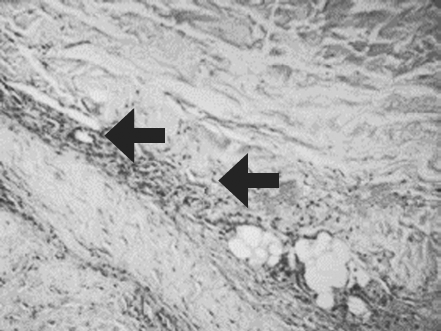

The results of three-year research on the use of allogeneic mesenchymal stem cells of adipose tissue (AMSCs) in the treatment of skin burns of II-III degree are presented. in a complex with wounds dressing of nanofibers chitosan and copolyamide, hyaluronic acid. It was found that with surgical necrectomy, introduction of AMSCs and substitution of defects with natural polymer coatings, the healing time is reduced by 89% (p < 0.05). Isolated administration of MSC reduces the healing period by no more than 5% (p > 0.05). The combined use of wounds dressings of nanofibers chitosan and copo lyamide with MSC accelerates the regeneration process by 26% (p < 0.05), with the introduction of AMSCs accelerating the development of granulation tissue by the fifth day of observation by 83% (p < 0.01). Joint use of wound coverings on the basis of hyaluronic acid with AMSCs is accompanied by an increase in the number of vessels of the microcirculatory bed in the defect area by 185% (p < 0.01). Clinical evaluation of the effectiveness of drugs with stem cells – a gel for topical application and a suspension of MSC LC for injection administration demonstrate their ability to optimize regeneration in the burn zone. Application of gel with AMSCs reduces the duration of epithelialization of border (dermal) burns by 2.2-2.4 times, with the final healing period being reduced by 59% (p < 0.01) and the suppuration frequency by 30% (p < 0.05). The introduction of a suspension of AMSCs into the zone of deep burn increases the frequency of engraftment of autografts, stimulates angiogenesis and proliferation of fibroblasts in the superficial and deep layers of the dermis. In the area of MSC administration, the LC perfusion level and the amplitude of blood flow fluctuation are twice as high as the values in the zones without the introduction of cells.